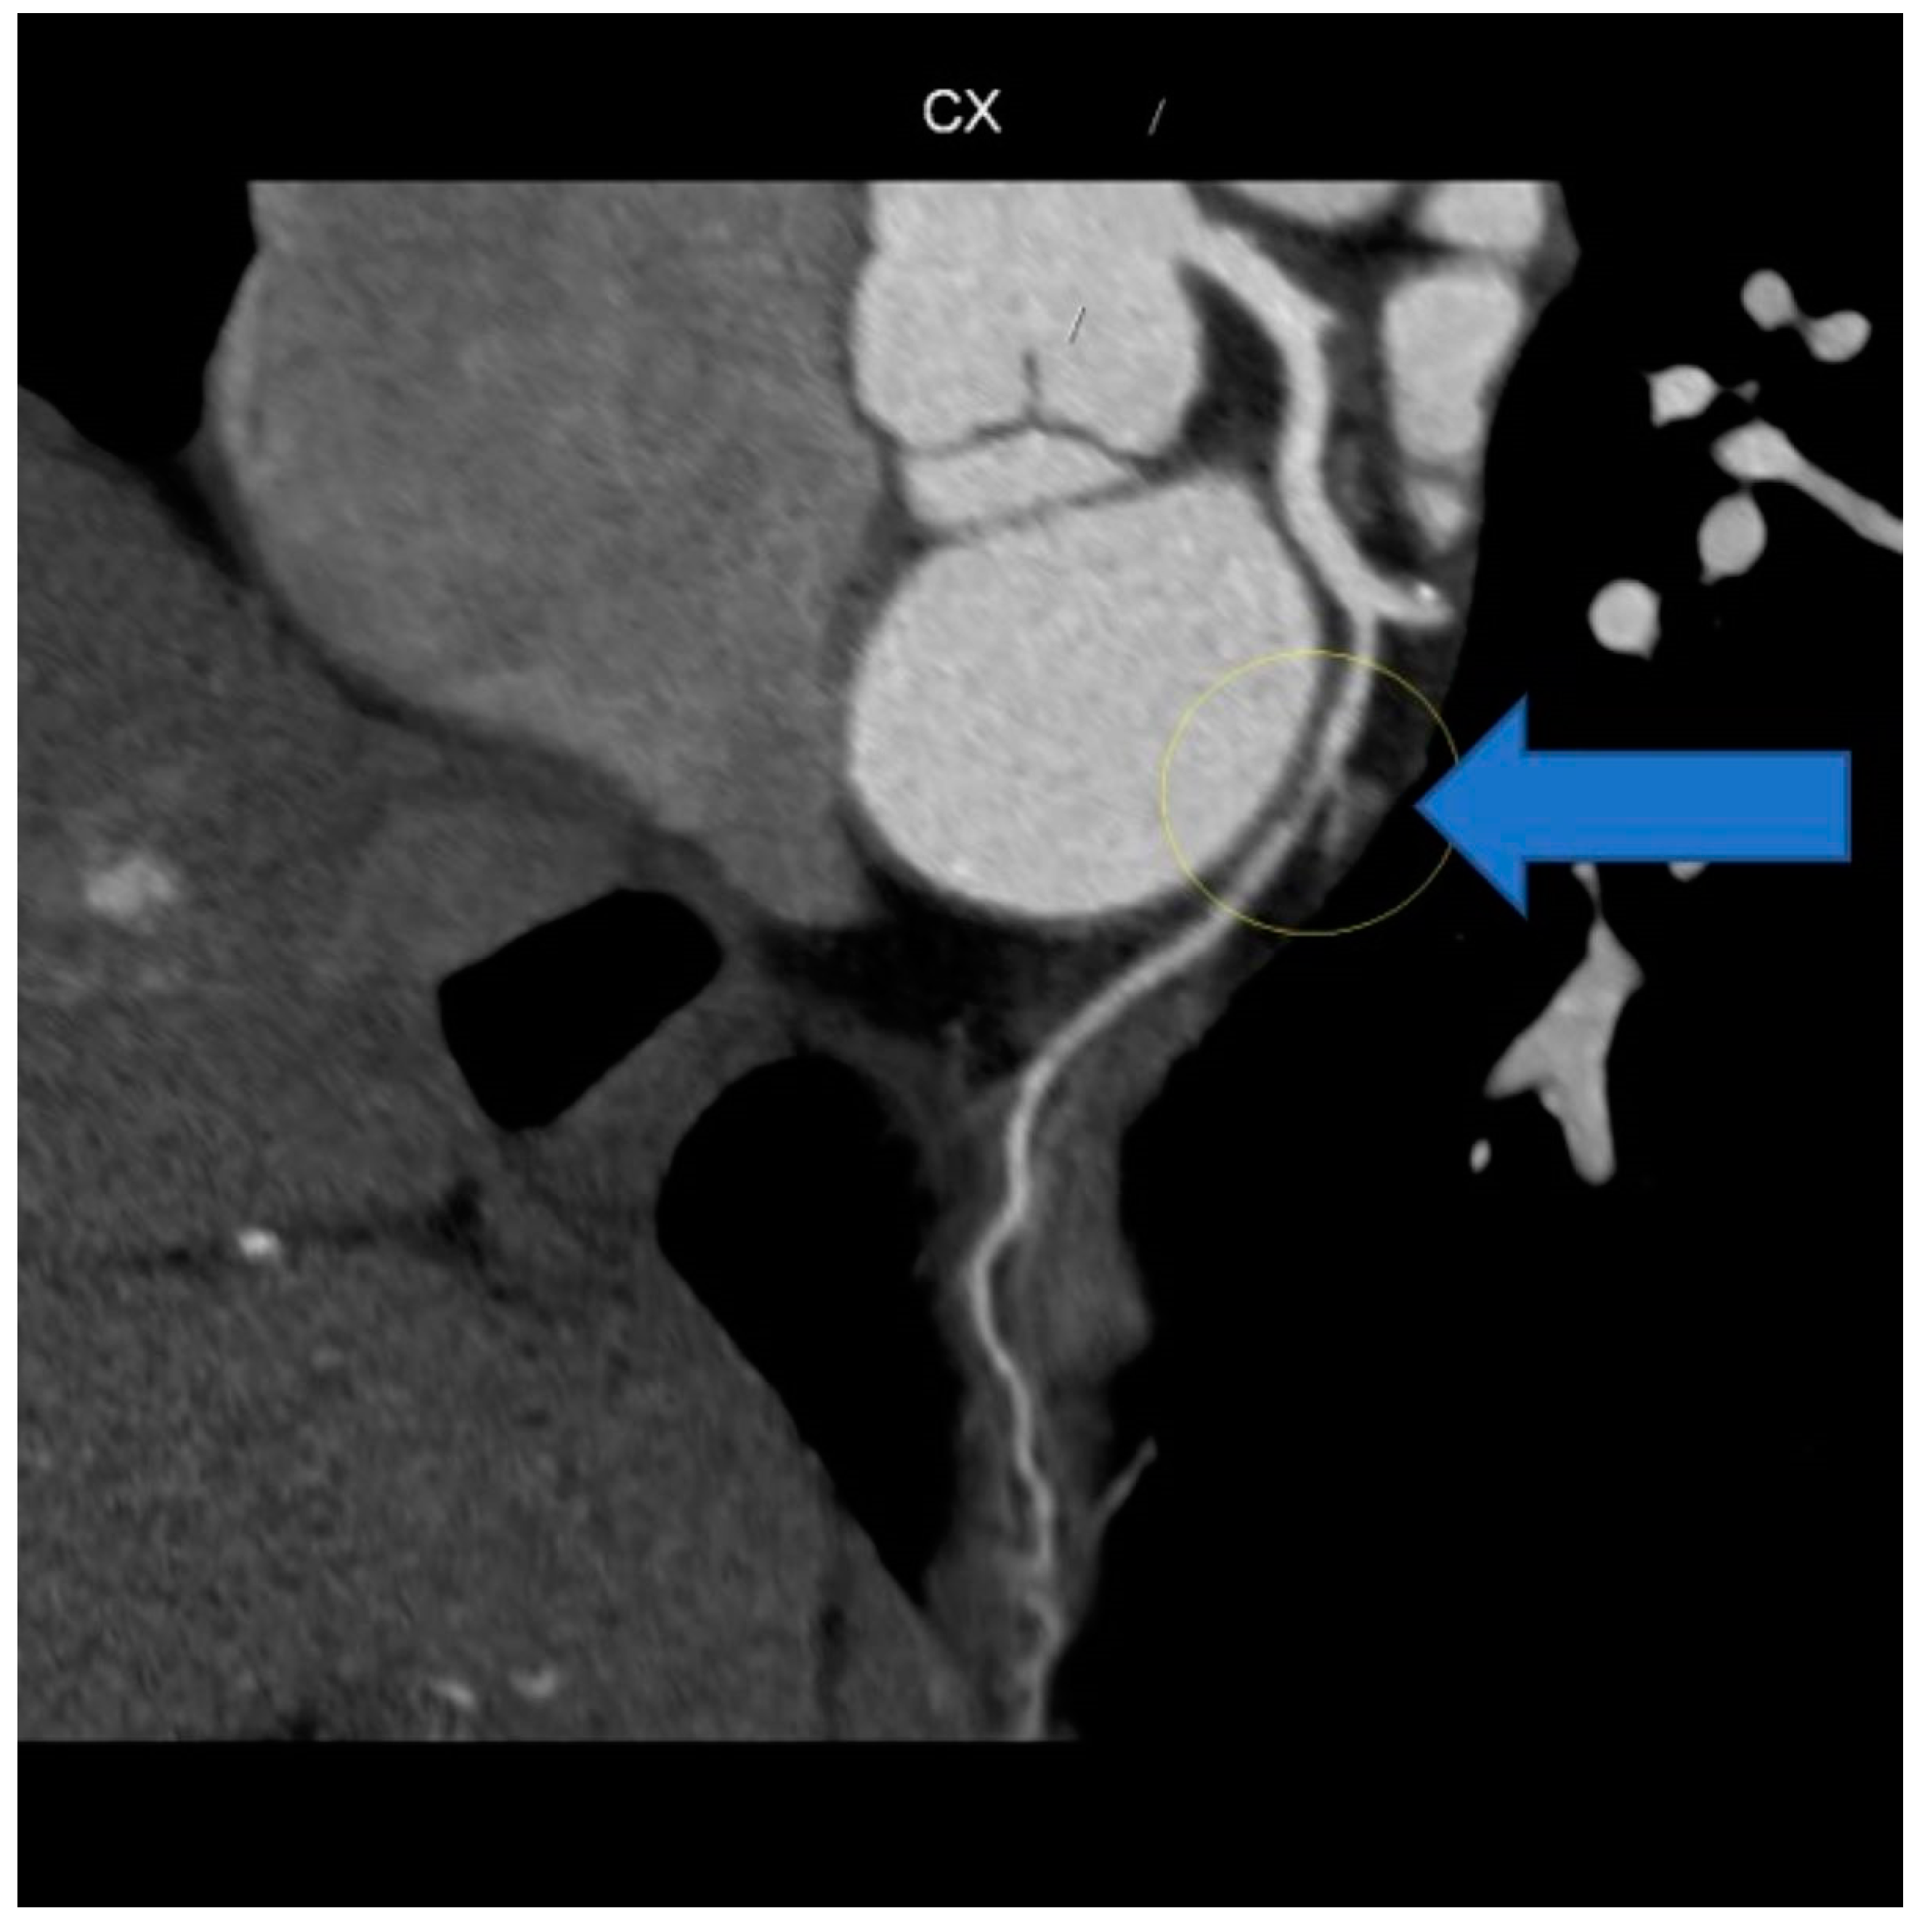

Due to the marked anxiety of the patient and the characteristics of the chest pain, a new multi-slice 128 × 0.5 mm ECG-modulated CT coronary angiography was planned, which revealed an average heart rate of 57 bpm; normal coronary artery origin; right-dominant coronary system; dominant RCA with a single calcific spot in the proximal segment, no significant stenosis; posterior descendent artery (PDA), posterior left ventricular artery (PL), and ramus intermediaris (RM) without stenosis; no atheromatous plaque; short, bifurcated LM, without stenosis; LAD and diagonals patent, without stenosis, no atheromatous formation; CX with a stenotic lesion in the middle segment, downstream of obtuse marginal artery (OM) origin, due to fibro-lipid plaque, approximately 50–60%; and OM with mixed stenotic atheromatous plaque at origin, 20–25%, while the rest of the course was patent, without stenosis (Figure 7).

Figure 6. CT coronary angiography showing normal appearance at the circumflex artery level (yellow circle).